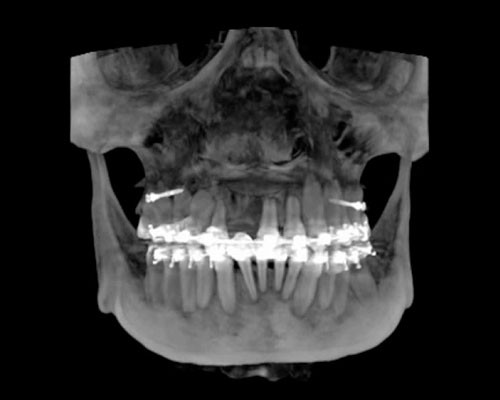

Precisión, eficiencia, calidad y oportunidad en todo el flujo de los tratamientos odontológicos

Exclusivo Sistema de Fotografía 3D disponible para todos nuestros clientes. IDM y Planmeca son pioneros en introducir este tipo de concepto en el Perú y consiste en la adquisición de una fotografía 3D sin necesidad de emitir radiación.